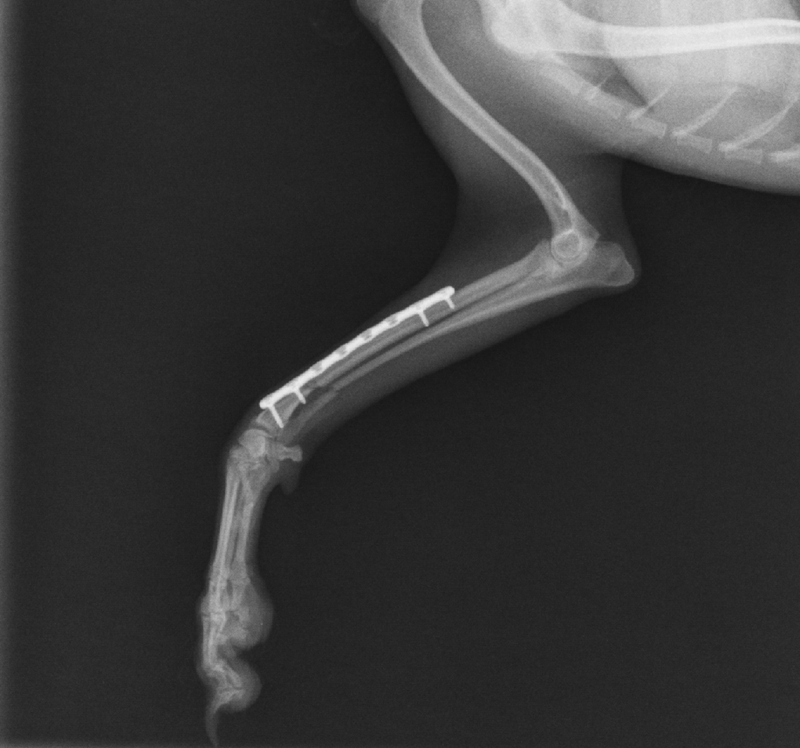

Ortopedija ili ortopedska kirurgija je grana kirurgije koja se bavi bolestima i liječenjem mišićno-koštanog sustava. Zbog kompleksnosti ozljeda pristup pacijentu je temeljit i sistematičan, a između ostalog uključuje opći pregled, promatranje kretanja, provjere opsega pokretljivosti i bolnosti, naposljetku se pristupa dodatnim dijagnostičkim pretragama kao što je rendgenološka pretraga. Najčešće ozljede uključuju prijelome kostiju i luksacije zglobova. Lom je svaki prekid kontinuiteta kosti, a luksacije su potpuna odvajanja krajeva kostiju koji se normalno spajaju u zglob. Glavni uzroci su prometne nezgode i padovi. Naša ambulanta koristi najmodernije implantate i tehnike sanacije dostupne u veterinarskoj medicini.